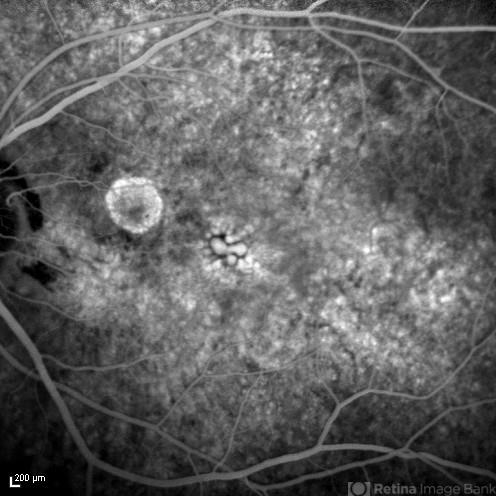

- rubella retinopathy, Spectralis

- Tom Steele, CRA

Optical coherence tomography system

spectralis - Description

- 48-year-old, deaf female, complains of blurry vision, mother had Rubella when she was pregnant.